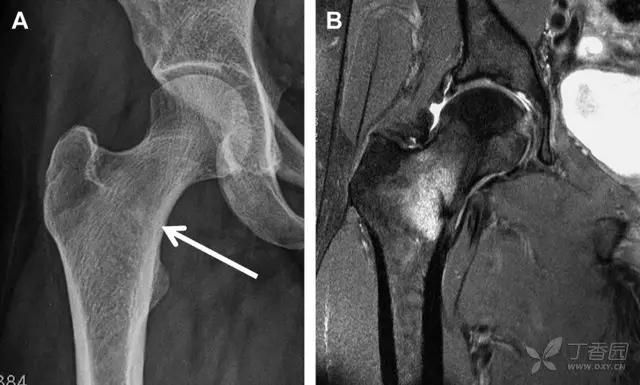

股骨头骨折

股骨头骨折常与髋关节脱位有关。需要注意的是那些既不是因剪力损伤也不是因直接*力暴**作用导致的骨折。这些类型的骨折可能十分轻微。提倡应用 CT 检查,不仅可诊断骨折,而且能评估关节内骨折碎片的位置(图 6)。

图 6 股骨颈骨折伴髋关节脱位。A 股骨头上外侧轮廓缺失(空箭头)注意嵌入上方关节间隙的骨折碎片(黑色箭头)B 冠状位 CT 多维重建(MPR)证实骨软骨碎片(白色箭头)和关节上方的另一个碎片(空箭头)

股骨颈骨折常发生在老年人,头下型骨折最常见,但是当股骨外旋或有明显的关节炎骨赘形成时,骨折较难发现。此外,肥胖和骨量减少增加髋部 X 片诊断难度,所以需格外注意。

因骨结构重叠影响,股骨转子骨折发生轻度移位时亦很难发现,加做一个不同角度的 X 线片有助于诊断(图 7)。

图 7 摔倒后股骨大转子骨折。A 正位片初步检查未发现明显骨折,进一步检查发现大转子上方皮质中断(箭头)。B 蛙式侧位片示骨折分离,尤其是后方(箭头)。初步检查时忽视了这一点,是因为股骨颈未能充分显示